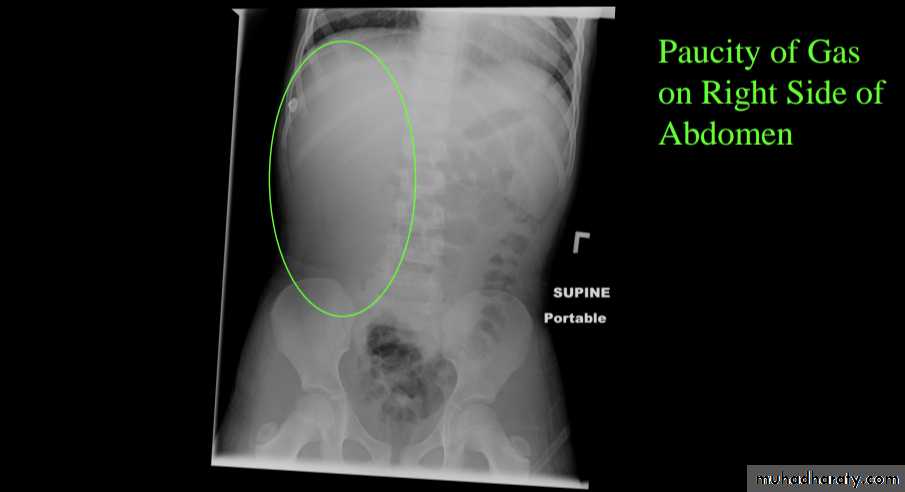

Abdominal plain film

Abdominal x-rays may demonstrate an elongated soft tissue mass (typically in the right upper quadrant in children) with a bowel obstruction proximal to it.